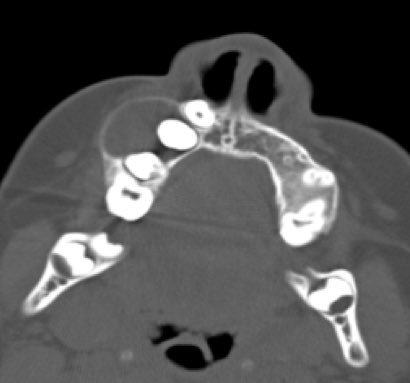

Odontogenic keratocyst (OKC)

قد يكون هذا من اكثر امراض الفك فيه اختلاف وجهات نظر وخيارات علاج متعددة وقد تغير اسمه مرتين عبر العقود الماضية. ولعل اكثر ما يميزه عن باقي تكيسات الفك هو كثرةعودة التكيس في الفك بعد علاجه اذا تم علاجه بالطريقةالتقليدية لتكيسات الفك باستئصاله فقط

٦)

OKC

تتراوح نسبة تكونه مرةأخرى بعد الاستئصال في الدراسات من٥-٥٠٪،وبالتالي يقتضي أن يتم تشخيصه اولا بشكل صحيح عن طريق خزعة وتقرير من قبل طبيب امراض الفم،وايضاعلاجه يقتضي إجراءات إضافيةبعد استئصاله من الفك لتقليل نسبةتكونه مرة أخرى

عادةيتم تشخيصه في مرحلةعمرية مبكرة(١٠-٤٠ عام)

١٥)

الغالبية من الحالات لا Ameloblastoma تظهر كتمدد في عظام الفك على هيئة مجموعة تكيسات متصلة وفي قليل من الحالات تظهر ككيس واحد متمدد داخل الفك والتشخيص يعتمد على نتيجة الخزعة (العينة)